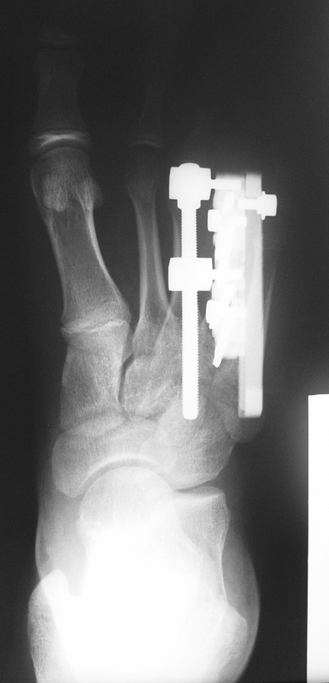

Doğuştan metakarp ve metatars kısalıklarının redavisi için pek çok teknik tanımlanmakla birlikte en çok akut uzatma sonrası kemik uçlarına greft konması ve distraksiyon osteogenezi (kallotasis) kullanılmaktadır. 1 cm.den daha fazla uzatma gereken olgularda kallotasis yöntemi önerilmektedir. Kliniğimizde de metatars ve metakarp uzatma için unilateral eksternal fiksatör ve sirküler eksternal fiksatör yardımıyla distraksiyon osteogenezi yöntemi tercih edilmektedir.